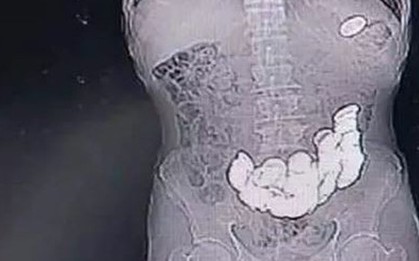

Bé gái 3 tuổi bị sốt cao, ho nhiều, được chẩn đoán viêm phổi và nằm viện gần 30 ngày nhưng tình trạng không thuyên giảm. Trong quá trình siêu âm, bác sĩ phát hiện ổ bụng trẻ có khối lạ nghi dị vật, lập tức chuyển bệnh nhi đến Bệnh viện Nhi đồng 2.